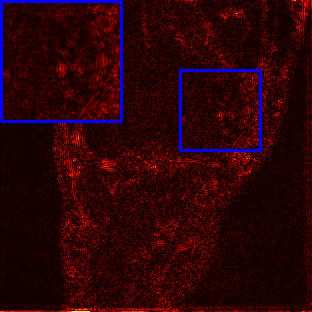

Limited by imaging systems, the reconstruction of Magnetic Resonance Imaging (MRI) images from partial measurement is essential to medical imaging research. Benefiting from the diverse and complementary information of multi-contrast MR images in different imaging modalities, multi-contrast Super-Resolution (SR) reconstruction is promising to yield SR images with higher quality. In the medical scenario, to fully visualize the lesion, radiologists are accustomed to zooming the MR images at arbitrary scales rather than using a fixed scale, as used by most MRI SR methods. In addition, existing multi-contrast MRI SR methods often require a fixed resolution for the reference image, which makes acquiring reference images difficult and imposes limitations on arbitrary scale SR tasks. To address these issues, we proposed an implicit neural representations based dual-arbitrary multi-contrast MRI super-resolution method, called Dual-ArbNet. First, we decouple the resolution of the target and reference images by a feature encoder, enabling the network to input target and reference images at arbitrary scales. Then, an implicit fusion decoder fuses the multi-contrast features and uses an Implicit Decoding Function~(IDF) to obtain the final MRI SR results. Furthermore, we introduce a curriculum learning strategy to train our network, which improves the generalization and performance of our Dual-ArbNet. Extensive experiments in two public MRI datasets demonstrate that our method outperforms state-of-the-art approaches under different scale factors and has great potential in clinical practice.